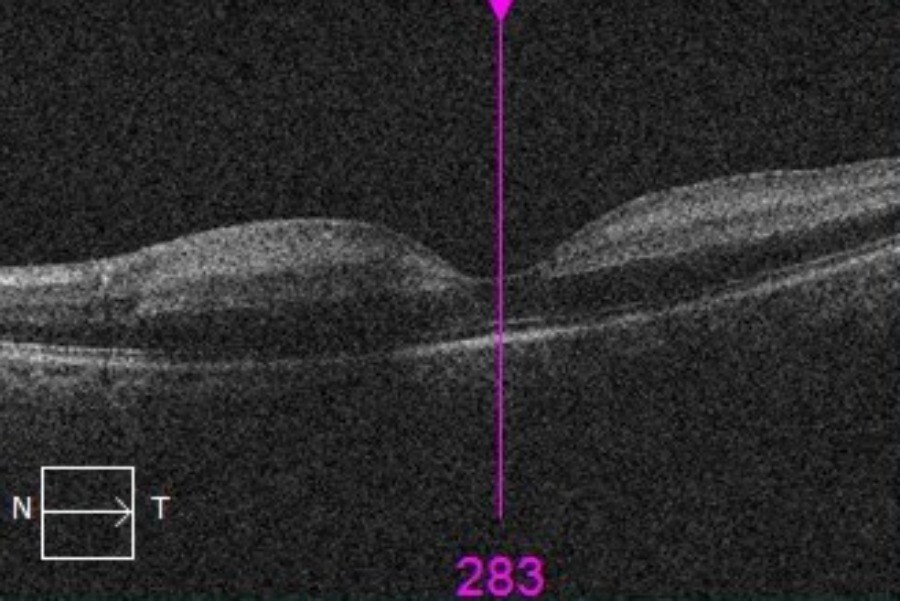

Optical coherence tomography of the left eye demonstrated increased retinal reflectivity and inner retinal thickening (Figure 3). Vital signs were within normal limits. No other focal neurological deficits were noted.